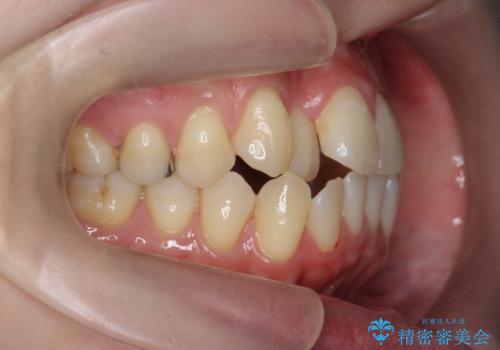

引っ込んだ前歯を並べたい マウスピースと部分ワイヤーのコンビネーション矯正

- 引っ込んで生えてしまっている前歯を並べたい、と矯正治療を希望され来院されました。

まずマウスピース矯正インビザラインシステムで、引っ込んだ歯が並ぶためのスペースを作ったのち、部分ワイヤー矯正を行い短期間での配列を計画します。

このように前歯の部分ワイヤーは引っ込んでしまった前歯や がたつきを素早く改善することができます。